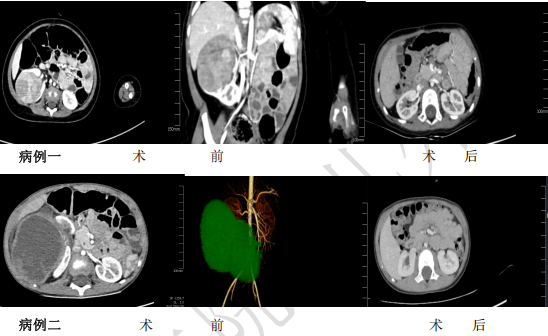

在儿童实体肿瘤诊疗技术飞速发展的今天,如何在根治肿瘤的同时,最大程度保护患儿器官功能、提升长期生存质量,已成为小儿外科肿瘤领域的关键发展方向。2023年、2024年,兰大二院小儿外科团队成功为两名肾母细胞瘤患儿实施了保肾手术。近日,术后复查结果令人欣喜:患儿肿瘤无复发,肾功能完全正常,身体状况恢复良好。这标志着兰大二院小儿外科在小儿肿瘤精准化、个体化治疗领域迈上了新台阶,实现了从“挽救生命”到“守护高质量生活”的重大跨越。

术前,团队充分利用先进的三维影像重建技术,对肿瘤位置、大小及与周围血管、组织的关系进行精准定位和评估,为手术规划提供“高清导航”,明确最佳切除范围。术中,凭借精湛的显微外科技术和丰富经验,医生们精细操作,在彻底切除肿瘤病灶的同时,最大限度保留了健康肾组织。术后,团队制定了严密的随访计划,密切监测患儿的恢复情况及各项指标。